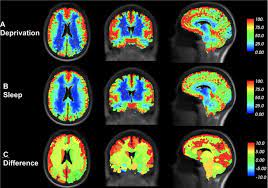

How Deep Sleep May Help The Brain Clear Alzheimer's Toxins

Jon Hamiltonnpr.org